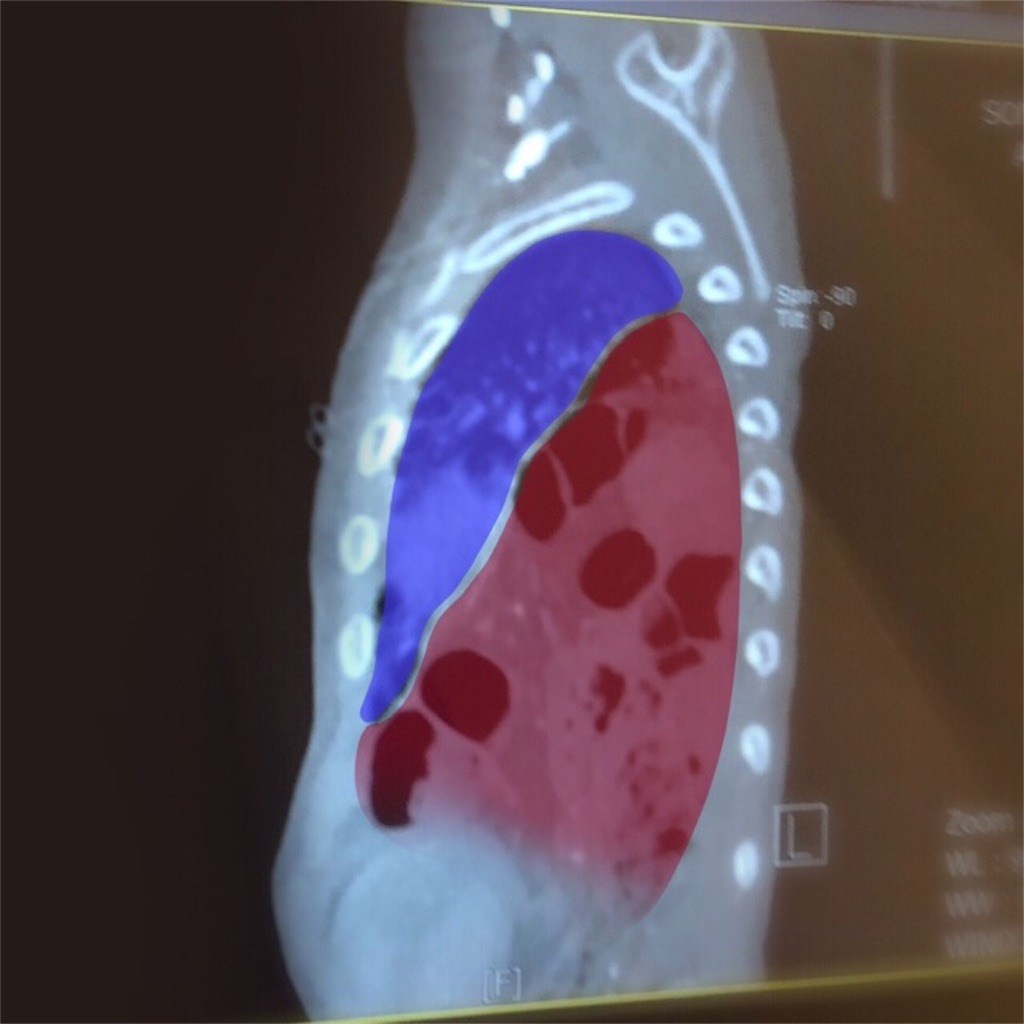

やはり、横隔膜に相当大きな穴があることがわかった。

本来、肺はこの青い部分のように胸骨いっぱいに広がっている。

赤い部分が横隔膜から飛び出た腸だ。

かなりの体積を占めているのが分かると思う。

半年前のCTでは分からなかったことだ。

衝撃画像……!